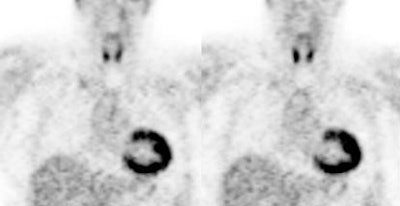

|

Myocardial activity: Myocardial uptake can be very variable. The patient on the left below had a glucose level of 97 prior to FDG injection. Despite the normal serum glucose, note the intense cardiac activity in this patient. The patient on the right was a diabetic patient with a blood glucose of 169- note that there is no myocardial uptake in this patient despite the elevated glucose level. |